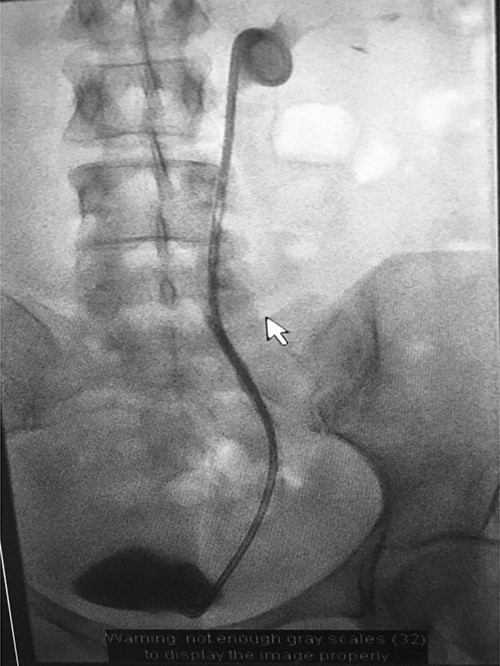

Under conscious sedation, using the previously inserted right percutaneous nephrostomy, antegrade access was achieved into the intrarenal collecting system and then into the proximal ureter. An 8 Fr × 11-cm access sheath was introduced. A guidewire was advanced antegradely through the site of ureteric transection and coiled in a position adjacent to the position of the guidewire that had been inserted retrogradely. A Gooseneck snare catheter was then passed over the guidewire and the snare was inserted (Figs 4 and 5). Under fluoroscopic guidance, the retrograde wire was retrieved and brought externally via the nephrostomy site, achieving through-and-through wire access (Figs 6 and 7).

Fluoroscopic images showing the antegrade Amplatz gooseneck snare catheter attempting to grasp the retrograde wire.